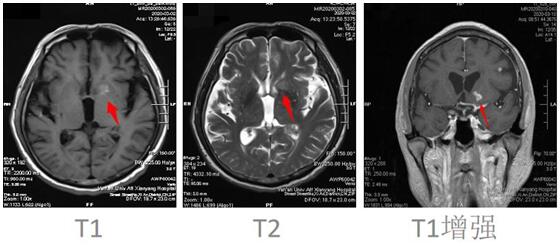

患者邱某,男,67岁 ,因“反复低热头痛40余天”入住我院神经内科三病区,入院后行神经系统体格检查示:表情淡漠,脑膜刺激征阳性;行颅脑磁共振增强扫描示:颅内可见多发点状及小片状结节灶,增强扫描呈小片状及环形明显强化,考虑①感染性病变,结核性脑膜炎可能,②转移瘤待排:请结合临床实验室检查;行腰椎穿刺术示:颅内压310mmH2O,潘氏试验阳性,并于脑脊液中检测出结核分枝杆菌(咸阳市首例)。脑脊液常规:淡黄色清亮,白细胞计数 210*106/L,潘氏试验阳性,中性粒细胞比率 90.0%。脑脊液生化:葡萄糖 1.40mmoI/L,氯 105.5mmol/L,微量总蛋白 2749mg/L,陈萍主任医师、代昌飞副主任医师及科室其他医师慎重讨论后考虑:结核性脑膜炎,并立即制定抗结核、降低颅内压、抑制脑水肿、减轻炎症反应等相关治疗方案。王宝艳护士长指导护理应加强护理,早期康复。经讨论汇总,为该患者制定特色治疗方案,动态调整,密切观察。在科室医生护士的精诚协作下,患者渡过险关。复查腰椎穿刺术:初压:170mmH20,常规:潘氏试验阳性;白细胞计数 120*106/L。淋巴细胞百分率 10.0%,中性粒细胞百分率 90.0%。生化:微量总蛋白 1503mg/L。出院后继续抗结核治疗。